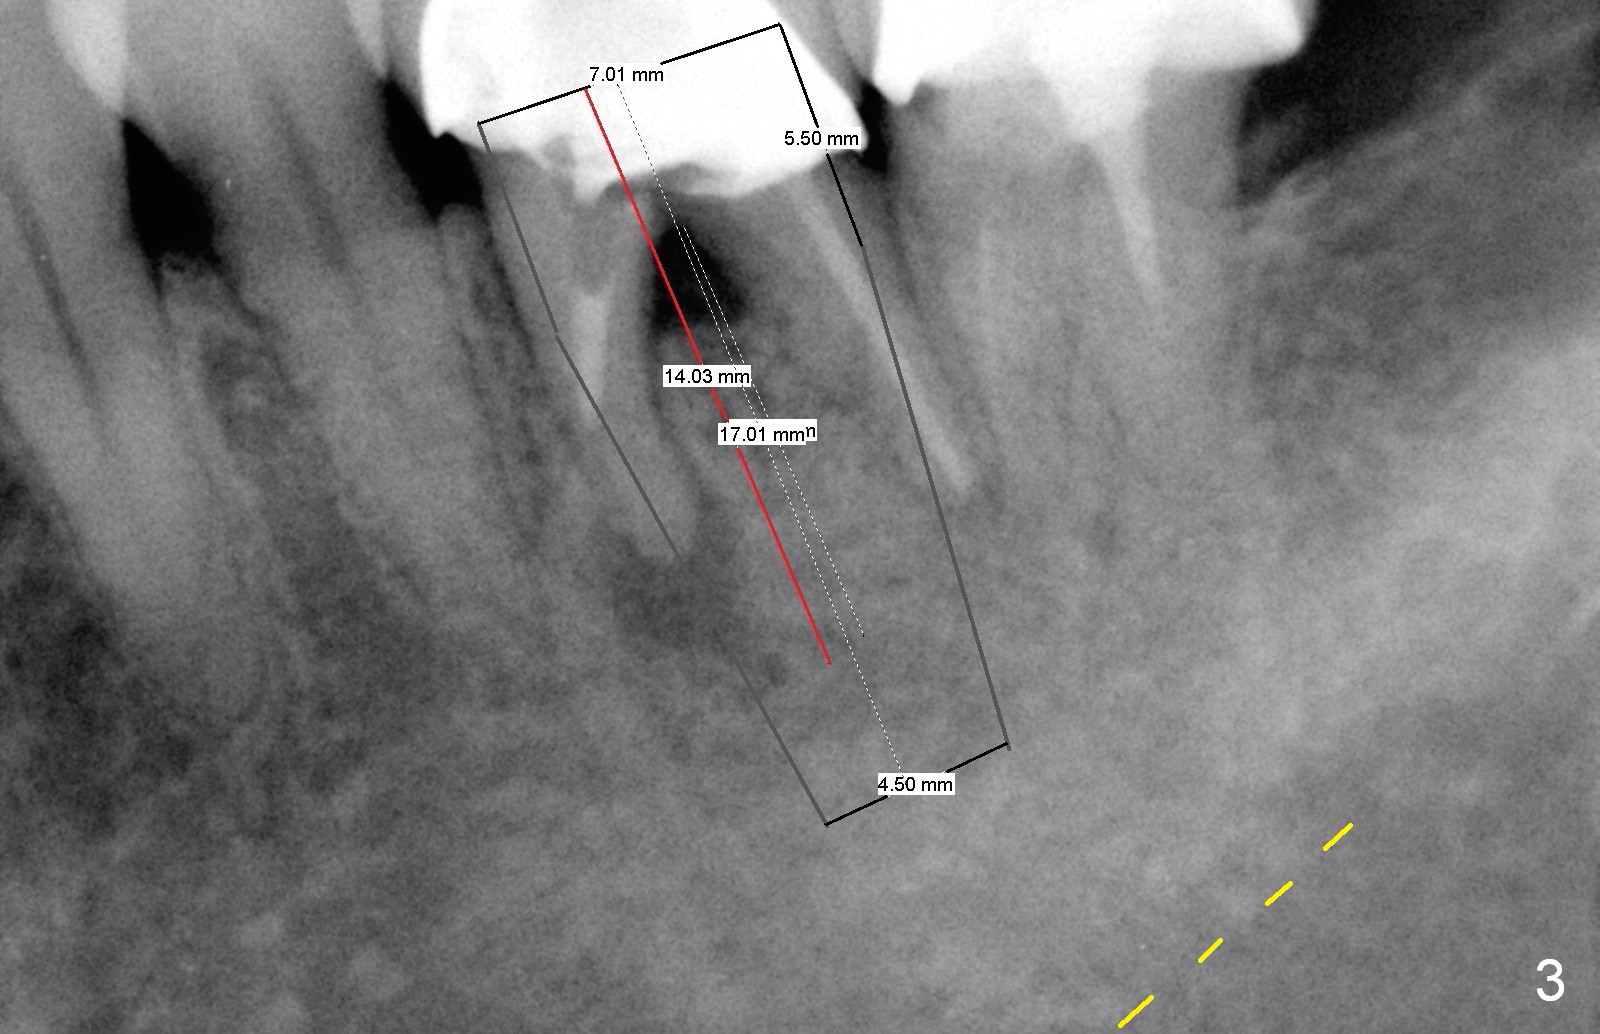

A 47-year-old lady lives out of town and presents to clinic with chief complaint "lower left back tooth easily bleeding with food impaction". Dental history and examination reveals failure of endo retreat of the tooth #19 (Fig.1), buccal gingival swelling (S), open access (A) and furcal and mesial periapical radiolucency (Fig.2 *). She is pleased to know availability of immediate implant and immediate provisional and accepts and receives the treatment at the same visit. The immediate implant (tissue-level) is designed to be as large as 7 mm and as long as 17 mm (Fig.3). To reduce paresthesia (yellow dashed line: the possible upper border of the Inferior Alveolar Canal)), a shorter implant (14 mm long in red line) is preferred. The tooth is extracted with sectioning. Granulation tissue is removed from the furca. The buccal plate appears to be intact. The septum is flat (Fig.4,10a S). Osteotomy starts in the middle of the septum with a 1.2 mm drill (Fig.10b red circle). As osteotomy increases in diameter (Fig.5 O), the apical end appears to be deviated mesiobuccally (Fig.10c large red circle). When a 6x17 mm tapered tap is being placed 14 mm deep (Fig.6 T), vibration of the buccal plate is seemingly felt at the apex (Fig.10d green circle). Further osteotomy may perforate the buccal plate. A 6x14 mm tissue-level implant is placed with >60 Ncm of insertion torque (Fig.7,8 I), followed by a 5x3 mm abutment (A) and bone graft (* in the remaining socket gap). An immediate provisional is cemented without occlusal contact (Fig.9 P).